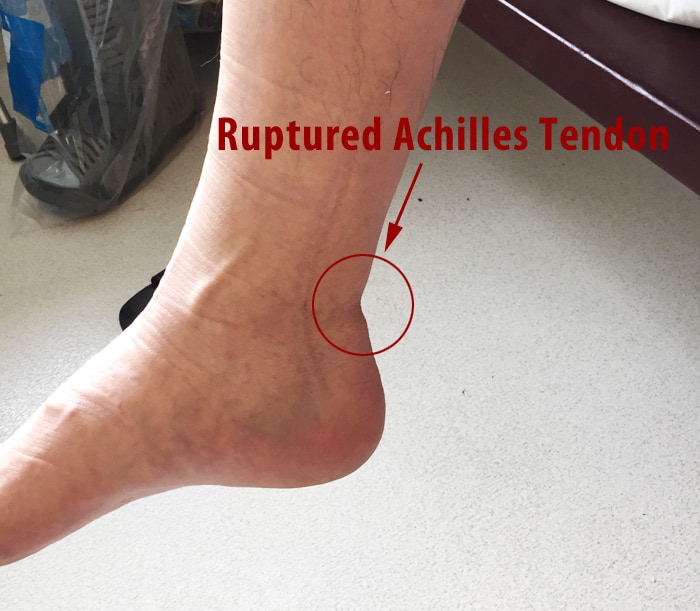

Achilles Tendon Rupture Information and Help SportNova UK – DaftSex HD

Achilles Tendon Tears | Jacksonville Orthopaedic Institute

Achilles Tendon Rupture – Orthopedic Institute of Sioux Falls

Achilles Tendon Rupture (Video) – Town Center Orthopaedics

How Do You Know if You Have Damaged Your Achilles Tendon? | Pinnacle …

Achilles Tendon Rupture – Causes, Symptoms and Treatment | Bone and Spine

Achilles Tendon Rupture stock illustration. Image of tear – 52456557

Achilles Tendon Rupture Non-Surgical Recovery and Proper Rehab – The …

Treatment of Achilles Tendon Rupture – Sports Medicine Review

Achilles Tendon Rupture | Tendon Pain | The London Foot & Ankle Clinic

Achilles Tendon Rupture – Core EM

Symptoms of a Torn Achilles Tendon | Healthy Living

Achilles Tendon Rupture – FootEducation

I ruptured my Achilles Tendon…The end of my YouTube Channel and Car Racing?